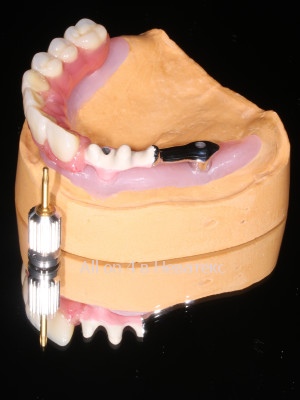

При изготовлении постоянного конструктива(начинки) протеза применяется технологичное литье MESA Magnum H50 с прессованием (Ti)титана 5 Grade. Отдельное и самое важное посещение пациента на 3 й день после операции - примерка гибридной балки гребнки, армирующей базу где распределяется пиковая нагрузка зубов - это и есть *скелет постоянной конструкции и основа привычных жевательных нагрузок.

5. После трех примерок логично дождаться, когда сойдет отек - это зависит от индивидуальной реактивности организма. На 5-7й день мы снимаем швы и плотно к мягким тканям (десне) фиксируем постоянный керамокомпозито-наполненный протез на винтах, точно повторив рельеф альвеолярного гребня (челюсти) и базы протеза. На 6 ти имплантах 14 зубов

Далее рассмотрим параметры введения протеза и что же все-таки такое балка и зачем она нужна. Самое важное условие при винтовой фиксации протеза к мультиюнит-аббатментам это его пассивное введение. Шахта титанового рукава в протезе должна четко и точно быть конгруэнтна шахте мультиюнит-абатмента. Введение болтика при винтовой фиксации и прикручивание протеза, не должно иметь внутреннего напряжения - дотяжка на 15 Н/см2 не должна иметь никаких боковых смещений. Также важно понимать, что на этом этапе, для успешного результата протез не дотягивается плотно к кости альвеолярного гребня, активно не дожимается, чтобы не было выталкивающего движения и негативного воздействия на незажившие имплантаты. Протез на первом этапе прилегает только к слизистой и функционирует на расстоянии зубной нити, между базой протеза и костными структурами гребня.

Керамокомпозито-наполненный диоксидом кремния протез на гибридной балке с титановой основой требует трех примерок после операции All-on-4 / All-on-6 и в отличии от металлопластмассовых адаптационных конструкций не требует перепротезирования

Литая балка в каркасе протеза армирована поясом на титановой основе, что значительно увеличивает прочность конструкции в целом.

Постоянный гибридный керамокомпозито-наполненный протез на ( балке-прототип Nobel Bar> включена в стоимость акции ), армирующей базу протеза, равномерно распределяет выламывающие горизонтальные тризмы, при переходе от адаптационных к постоянным нагрузкам, считается постоянной конструкцией для долгосрочного использования.